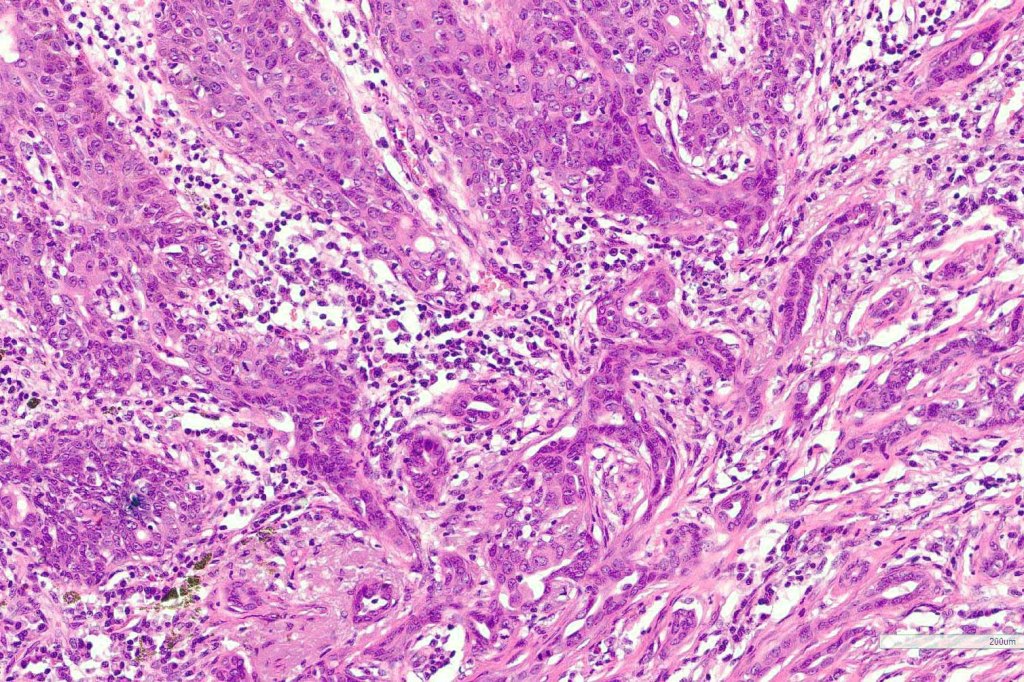

•Widely infiltrating biphasic tumor

•Superficial SCC

•Adenocarcinoma in deeper reaches

•Variable pleomorphism and mitotic activity

•Often extends to the subcutaneous fat

•Perineural infiltration is commonly seen